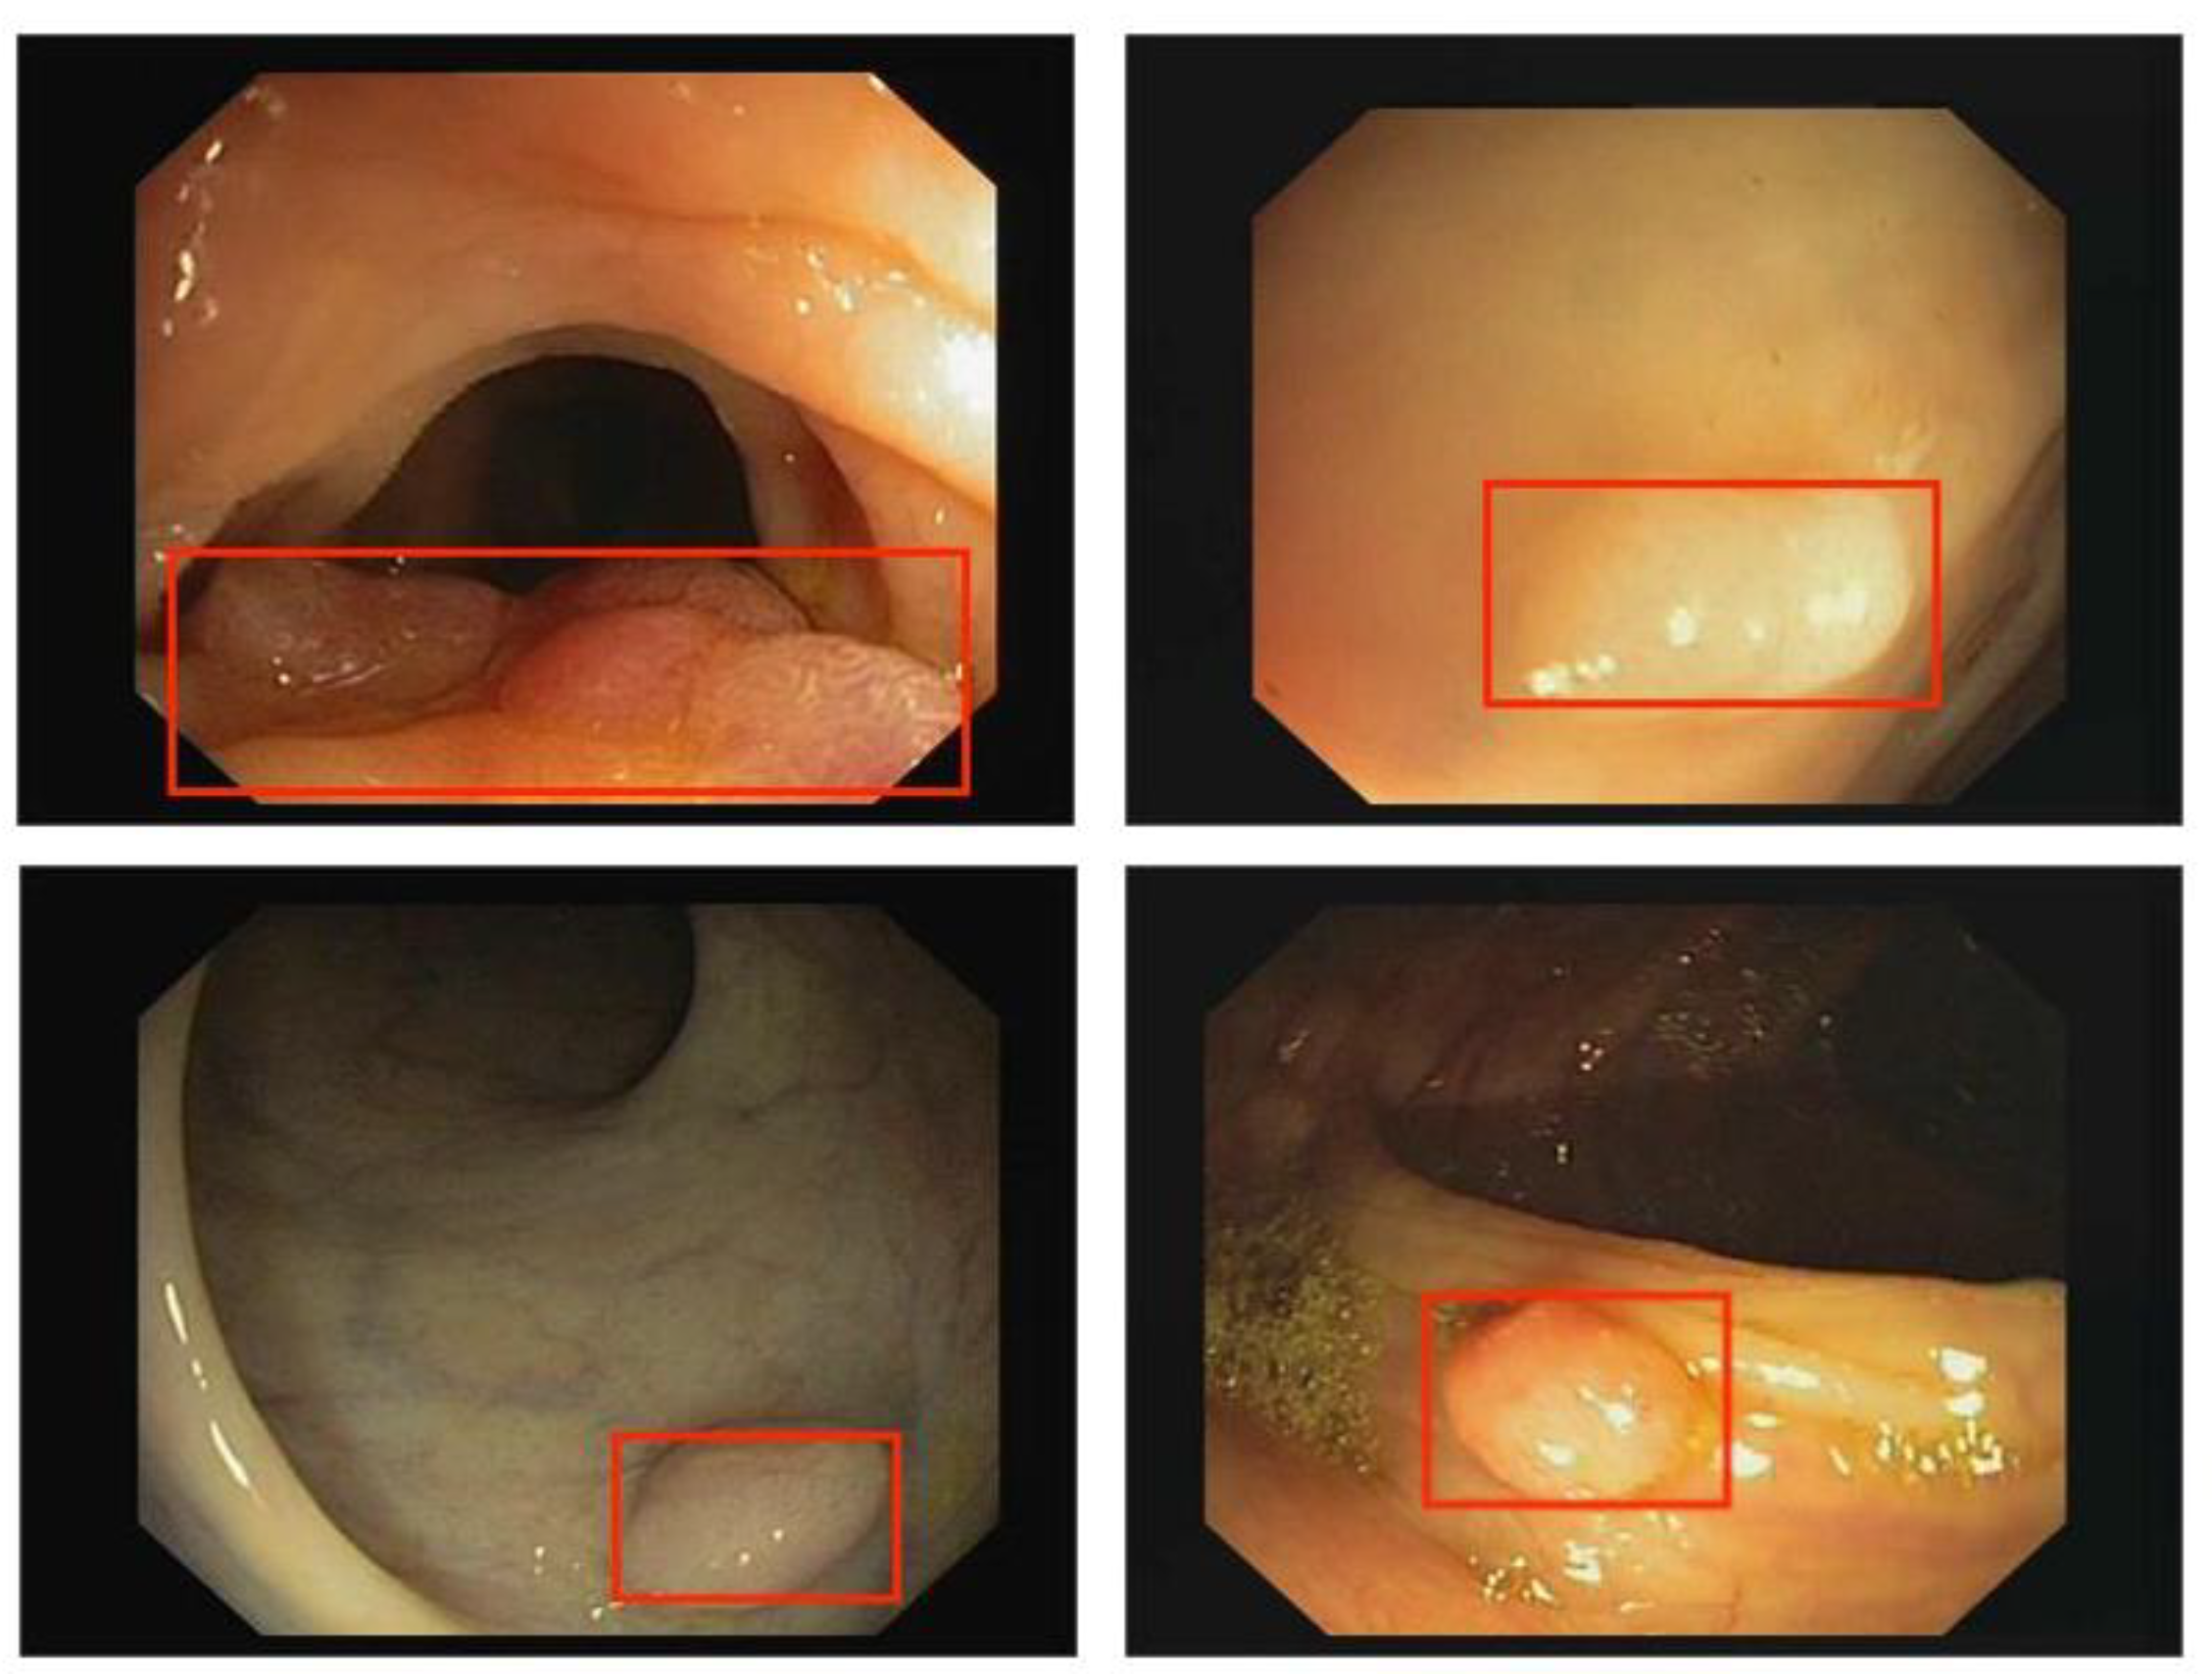

- In order to realize the calculation of areas with fuzzy saliency scores in the case of various polyp locations and the presence of fuzzy areas that are easily confused with polyp areas, a contextual attention module is implemented by combining foreground and background areas. In this paper, a simple parallel axial channel attention is proposed so as to correctly identify polyps from the background region.

4.1. Experimental Datasets and Evaluation Metrics